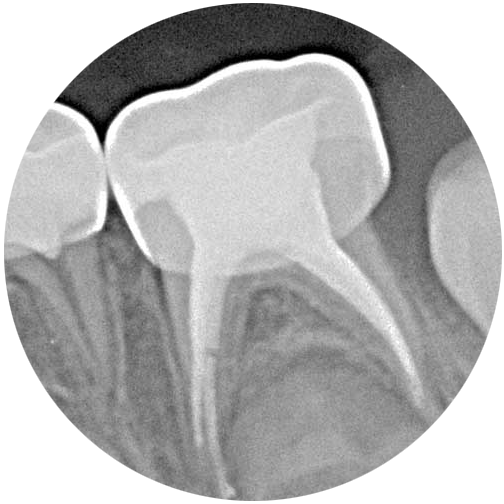

MILCHZAHNWURZELBEHANDLUNG

Aufgrund der natürlichen anatomischen Eigenschaften eines Milchzahns – wenig Zahnschmelz und ein sehr großer Nerv – wird eine Milchzahnwurzelbehandlung sehr viel schneller nötig als am bleibenden Zahn.

Eine so genannte Wurzelamputation, bei der nur der obere Teil des Nervs entfernt wird, ist in der Kinderbehandlung eine sehr häufige Maßnahme, die schnell und unproblematisch durchgeführt werden kann. Seltener wird eine komplette Wurzelbehandlung nötig.